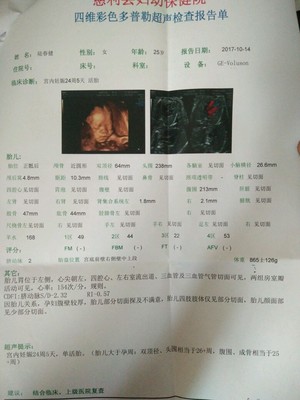

在这么多的产前检查项目中,在孕六个月左右做四维彩超是非常重要的,因为医生可以通过屏幕直观地观察到胎儿的面部、心脏、以及其他内脏器官,胎儿的所有器官在孕22周就已经发育完成,孕24周就可以清晰地看到。如果有什么异常,是可以发现的。

建议孕20周后做胎儿四维彩超。2.胎儿的四肢和主要器官在怀孕20周后已经全部发育完成。最佳检查时间为孕24周、28周,因为这个阶段胎儿结构已经形成,胎儿大小和羊水适中,胎儿骨骼回声相对较小,图像清晰。所以这个时期是胎儿畸形检测最理想的时期,通过检查可以排除大部分畸形。四位彩色多普勒超声使用的仪器称为“四维彩色超声诊断仪”。

一般来说,妊娠2428周是四维彩超的最佳时间,因为胎儿24周左右是大脑快速发育的时期,这期间胎儿结构已经形成,胎儿大小和羊水适中,在子宫内的活动空间较大,胎儿骨回声的影响相对较小,图像相对清晰。四维超声在三维超声的基础上具有实时动态效果。准爸爸和准妈妈可以通过屏幕见证宝宝在妈妈肚子里的运动、呼吸、吞咽、打哈欠、吐舌头等生理活动,非常直观。

四维彩色多普勒超声是目前世界上最先进的超声诊断技术,可以从多个方向和角度观察宫内胎儿的生长发育情况,达到最佳的检测效果,为临床诊断提供准确的科学依据。一般来说,彩色多普勒超声的异常分为两个阶段。第一阶段为ⅱ类异常,在孕1822周时进行。四维是畸胎学的第二阶段,筛查的最佳时间是孕2228周,因为这一时期胎儿的四肢和主要器官已经全部发育,羊水更适合胎儿畸形筛查。